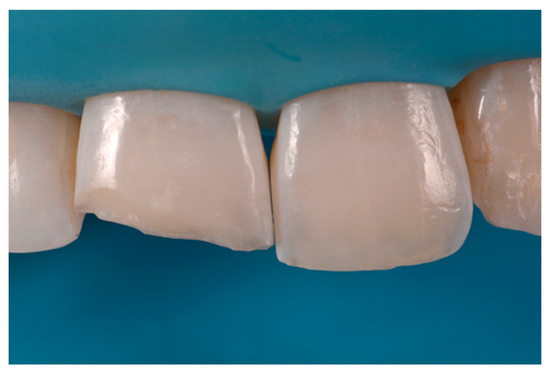

A 27-years lady presented to the dental office after traumatic accident (Figure 30). Tooth #1.1 responded positively to pulp tests (cold and electrical) while Tooth #2.1 showed pulp exposure and continuous bleeding. Endodontic treatment was therefore performed on #2.1 (Figure 31) and direct restoration of both teeth was planned. Shade was selected as described in previous case, using the button-try technique [14]. Even in this clinical case, considered the sufficient ferrule, no post was applied on Tooth #2.1. After isolation and preparation (Figure 32), adhesive procedures were performed using a self-etch two-step adhesive with selective etching procedure (Clearfil SE, Kuraray Noritake Dental, Tokyo, Japan).

Once completed, the two frames (Clearfil Majesty ES-2, A1E, A2D, Kuraray Noritake Dental, Tokyo, Japan) showed internal and external excesses that were reduced using diamond burs and discs (Figure 33 and Figure 34) strictly following the procedure described in Section 2.1.2 of present article. Excesses were removed from the distal-incisal angle of #2.1 allowing therefore to obtain the desired translucency. After silane application and bonding procedure (Figure 35) as described in Section 2.1.2, restorations were completed (Figure 36 and Figure 37). They both show satisfactory clinical integration 1.5 years post-operative (Figure 38 and Figure 39).

Figure 33.

Frame imprecisions are corrected by reducing interproximal wall from the internal side. Reprinted from Restauri diretti nei settori anteriori, G. Paolone, S. Scolavino, © 2021, with permission from Quintessence Publishing Italy.

Figure 34.

Frame is also trimmed reducing external outline. Reprinted from Restauri diretti nei settori anteriori, G. Paolone, S. Scolavino, © 2021, with permission from Quintessence Publishing Italy.